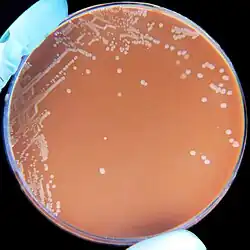

| H. influenzae on a chocolate agar plate | |

Bacterial culture of H. influenzae is performed on agar plates. The strongest growth is seen on chocolate agar at 37 °C in a CO2-enriched incubator.[33] The ideal CO2 concentration for the culture is ~5%.[34] However adequate growth is often seen on brain-heart infusion agar supplemented with hemin and nicotinamide adenine dinucleotide (NAD)

Colonies of H. influenzae appear as convex, smooth, pale, grey, or transparent colonies with a mild odor.[34] H. influenzae will only grow on blood agar if other bacteria are present to release these factors from the red blood cells, forming 'satellite' colonies around these bacteria. For example, H. influenzae will grow in the hemolytic zone of Staphylococcus aureus on blood agar plates; the hemolysis of cells by S. aureus releases NAD which is needed for its growth. H. influenzae will not grow outside the hemolytic zone of S. aureus due to the lack of nutrients in these areas.[35]